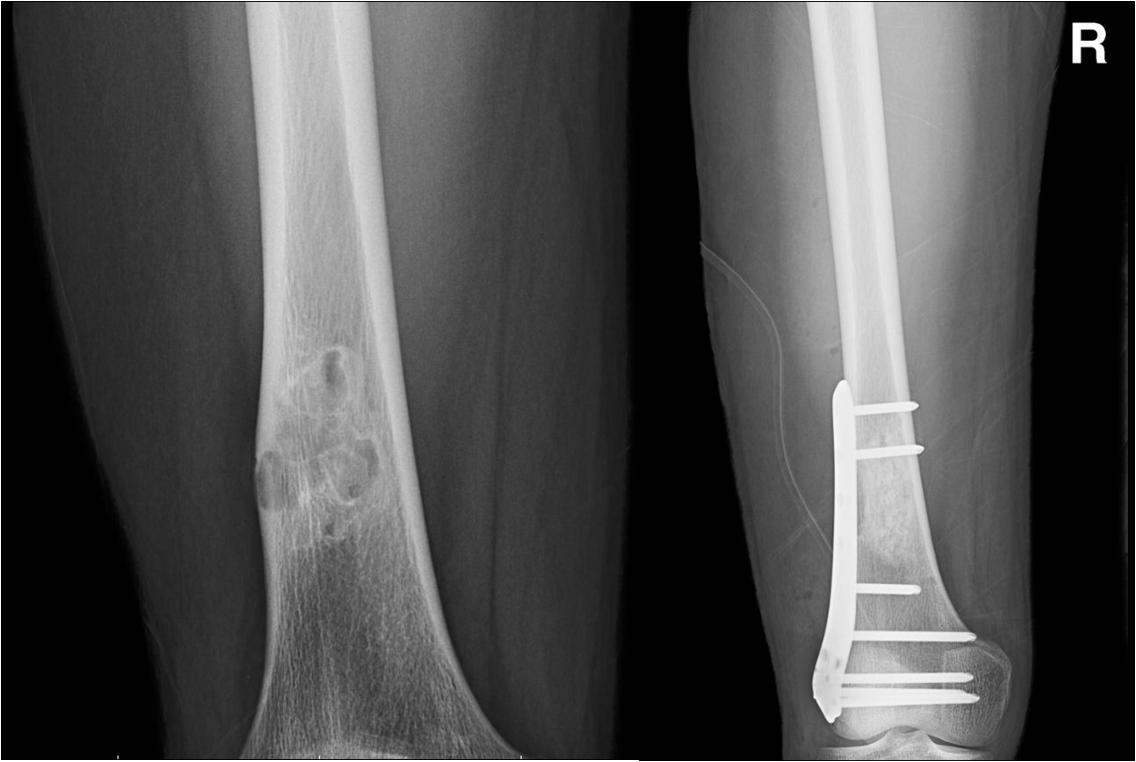

骨折、骨折延迟愈合

骨折作为创伤骨科最为常见的疾病,其治疗早已有标准化的流程,但近年来联合使用PRP的治疗方式逐步在临床中得到应用 。

Namazi等对30例桡骨远端关节内骨折患者进行随机试验研究,进行闭合复位内固定后试验组给予关节内PRP注射治疗 ,发现随访3个月时腕关节屈伸功能以及随访6个月时VAS、特定活动和常规活动评分均有所改善。

这表明PRP可显著减少桡骨远端关节内骨折后的疼痛和活动障碍。 Singh等前瞻性研究了PRP联合交锁髓内钉对外伤性股骨干骨折患者的疗效,发现PRP对闭式髓内钉治疗股骨干骨折无影响;

然而,在开放或闭合髓内钉治疗失败时,PRP可能在愈合初期通过提供人工血肿效应进而促进骨折愈合 。除了应用PRP治疗新鲜骨折外,也有研究表明PRP可促进肱骨延迟愈合患者早期骨巩固。